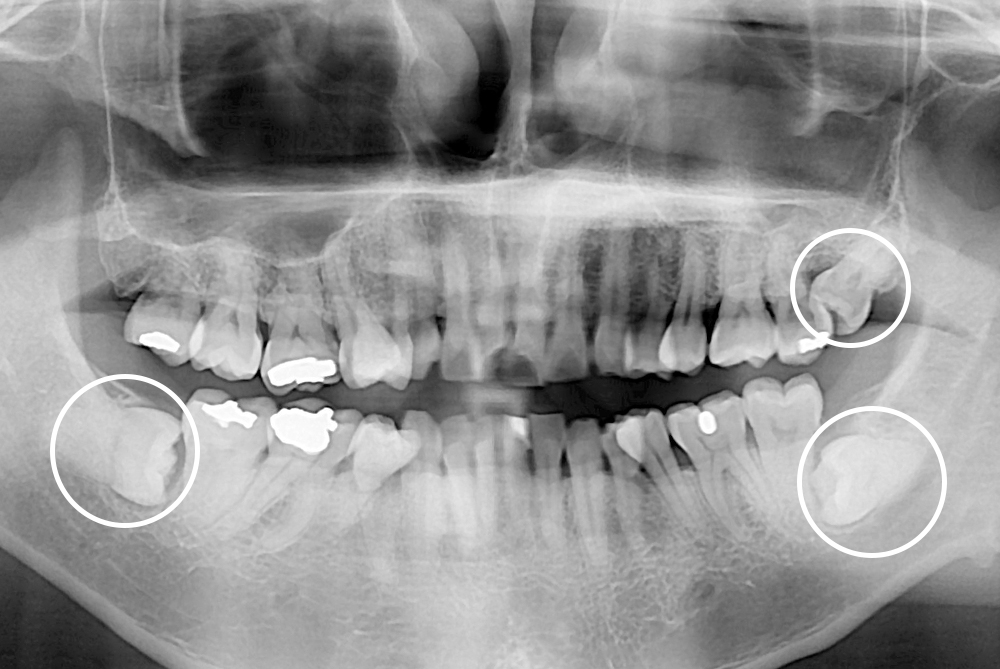

[사랑니] 매복 사랑니 발치

치료후 : 2020-03-27

세종치과는 구강악안면외과학 박사이신 원장님이 발치하는 치과입니다.